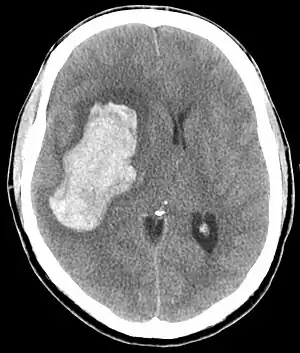

| CT scan of an intracranial hemorrhage, a possible complication of hypertensive emergency. | |